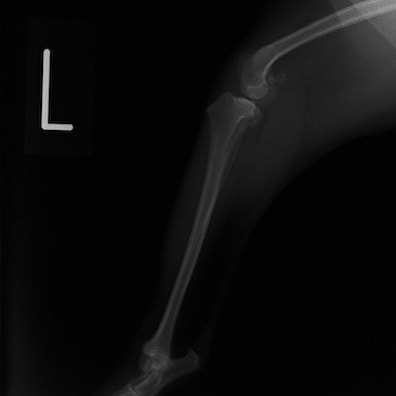

■ 症例20 ポメラニアン 8ヶ月 1.8kg

左右膝蓋骨脱臼 グレードⅢ

2ヶ月前から間欠的跛行が認められ、両膝の膝蓋骨脱臼整復術を行った。

手技は縫工筋及び内側広筋の解放、脛骨粗面の外側転位、滑車ブロック形造溝術、内外側関節包の縫縮を選択し実施した。

右側の膝蓋骨脱臼は上記手技で整復されたものの、左側はそれのみでは膝蓋骨が浮く様子が認められた。その為、PDS縫合糸にて膝蓋靱帯を1糸のみ縫合し、靱帯の縫縮を行った。

膝蓋骨脱臼は膝関節における膝蓋骨の内外側の脱臼と定義されるが、時として単純な内外の脱臼ではなく、膝蓋骨が大きく前方に浮き上がるように脱臼する場合がある。特にトイプードルやポメラニアンといった犬種に多く認められる。

内側脱臼に加えて前方への浮き上がりを矯正する為に、従来より脛骨粗面転移により膝蓋靭帯を外方と下方に引っ張り、固定する方法を選択する。膝蓋骨の前方への浮き上がりが軽度の場合は、従来法ではなく関節包の縫縮で対応していた。しかし、一部の症例で膝蓋骨の動きが悪くなり伸展機構が円滑に機能せずロボット様歩行になるケースがあった。

その為、膝蓋靭帯自体を縫縮する方法を採用した。この方法により、膝関節の伸展機構を妨げず膝蓋骨の軽度の浮きを矯正することが可能となった。

本症例の経過は良好である